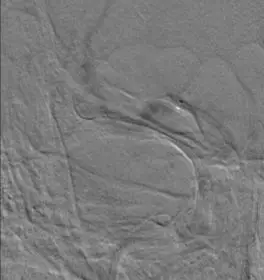

诊断分析 右侧颈内动脉C1段闭塞合并右侧大脑中动脉M1段闭塞。拟行支架机械取栓治疗。 治疗情况 耗材:8F血管鞘,8F导引导管,Navien 5F颅内支撑导管,Rebar-18微导管,0.014微导丝,Solitaire 4-20支架,SpiderFX保护伞,5-40球囊、1.5-20球囊,2-20球囊,9-40 Protégé。 支架: 1. 开通右侧颈内动脉C1: 通过1.5以及2.0球囊对C1段依次进行扩张,可见C1重度狭窄。

5mm Spider保护伞到位。

通过5.0mmX40mm球囊扩张C1段,恢复颈内动脉血流。